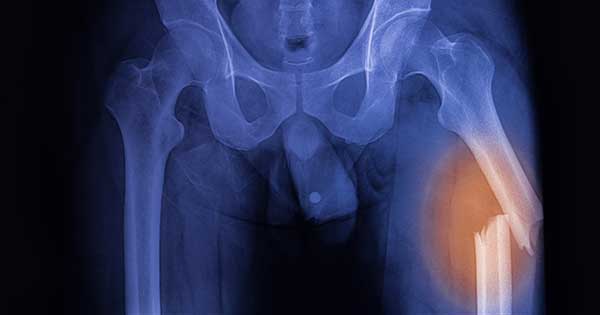

El fémur, o hueso del muslo, es considerado el hueso más grande y más fuerte de todo tu cuerpo. Cuando el fémur se fractura (es decir, se rompe), le lleva mucho tiempo sanar por completo. Romperse el fémur puede hacer que las tareas diarias sean mucho más difíciles porque es uno de los principales huesos que se usan para caminar.

El fémur es un hueso muy grande y fuerte que es difícil de romper. Una fractura de fémur generalmente es causada por un accidente severo. Los accidentes causados por vehículos, como los choques a alta velocidad, son una de las principales causas.

Los adultos mayores pueden fracturarse el fémur por una caída debido a que sus huesos tienden a ser más débiles. Dependiendo de qué tan cerca de la cadera esté la fractura, puede llamarse fractura de cadera en lugar de fractura de fémur.